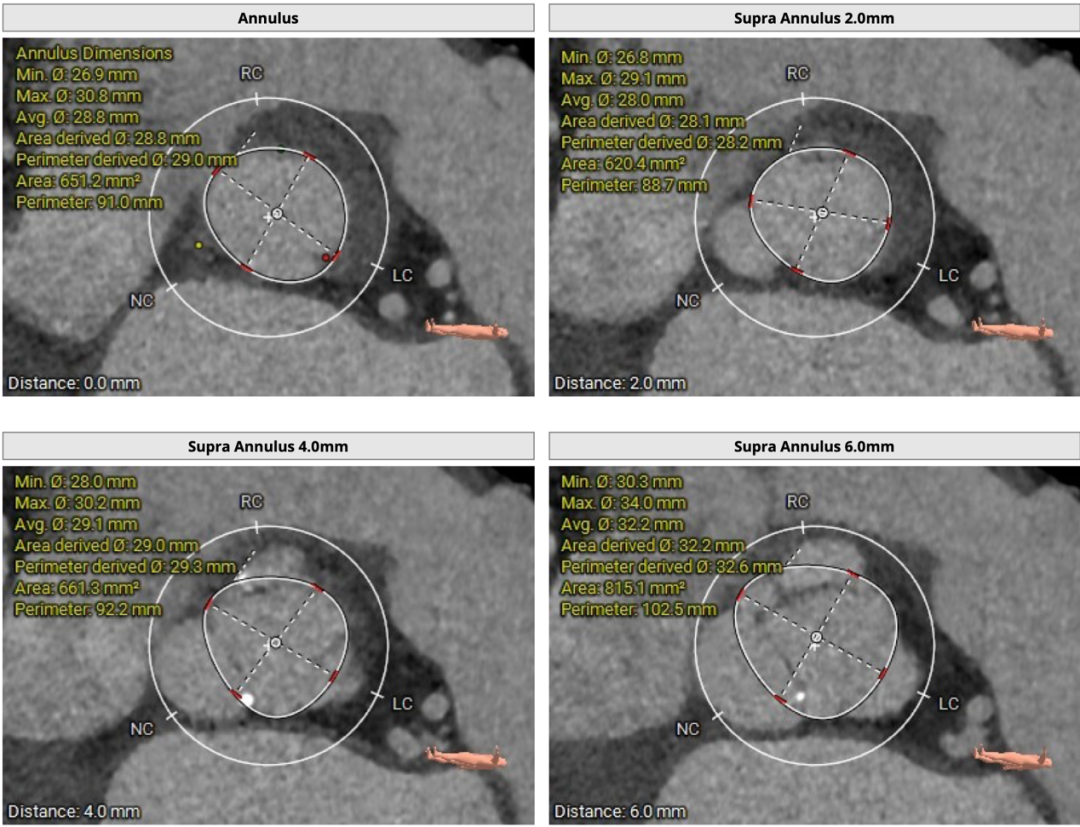

71岁男性,主动脉瓣轻度狭窄重度反流。三叶瓣,左右交界有钙化,瓣环均径29mm,LVOT均径28.9mm,瓣上6/8mm预计展开均径分别是26.6mm/27.2mm,左冠高度19mm,右冠高度25mm,STJ均径31mm,升主均径35mm患者室壁较厚,高度26mm,窦宽38/37/39mm,升主均径约34.1mm,左室壁较厚,心尖部室壁厚约4mm。此外,右侧入路较窄处内径约7.5mm,右侧髂外、主动脉弓见少许钙化强回声,腹主动脉部分节段走行稍扭曲。心尖部室壁较薄,主动脉根部解剖结构偏极限,对临床团队术前评估及术者术中精准释放有很高要求。

该患者为大瓣环反流,左右交界有钙化,拟植入Vita Flow® 30瓣膜,瓣下2mm释放。